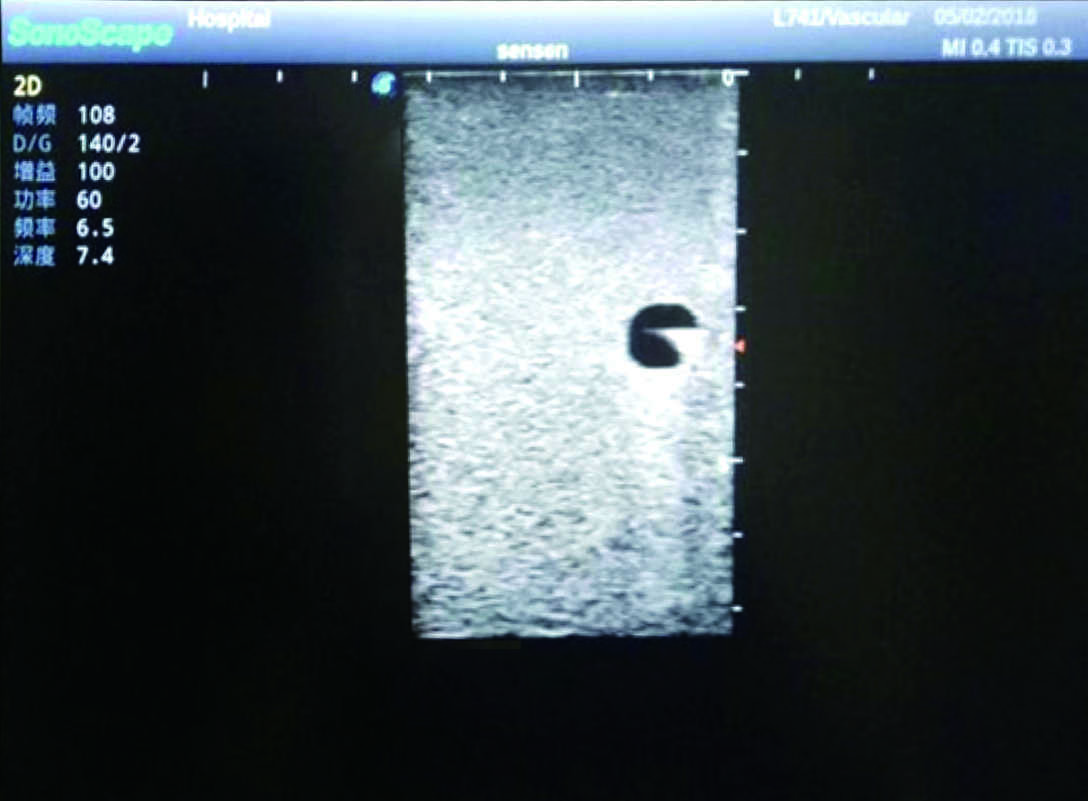

PICC Ultrasound Training Model

Model TYE1510.1

Outline

It is a model covering up from lobulus auriculae plane to the umbilical plane, and it has anatomical structures like clavicle, rib, sternocleidomastoid, jugular vein and basilic vein.

1)   Made of high molecular polymer ultrasound material, close to the real skin

2)   It can be used by real ultrasound machines

3)   Clear and real images of the tissues and organs (basilic vein and superior vena cava)